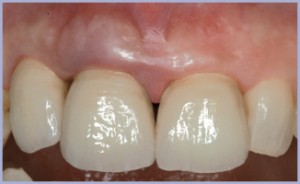

Alla consegna il moncone è stato inconato con l’apposito percussore (figg. 39, 40) e le corone definitivamente cementate (figg. 41, 42, 43, 44).

I tessuti molli hanno avuto per la loro maturazione lo stesso periodo di tempo concesso alla osteointegrazione e si presentano pertanto, alla rimozione del tappo di guarigione, spessi e privi di sanguinamento (figg. 13, 14, 15).

Alla seconda seduta, dopo un periodo di sei mesi (figg. 11, 12), una rx di controllo ha evidenziato la buona osteointegrazione dell’impianto e, soprattutto, il perfetto mantenimento dell’osso a livello crestale, senz’altro favorito dalla tecnica chirurgica atraumatica e dall’assenza di gap presente all’interfaccia moncone-impianto, tipico di un sistema ad accoppiamento conometrico.